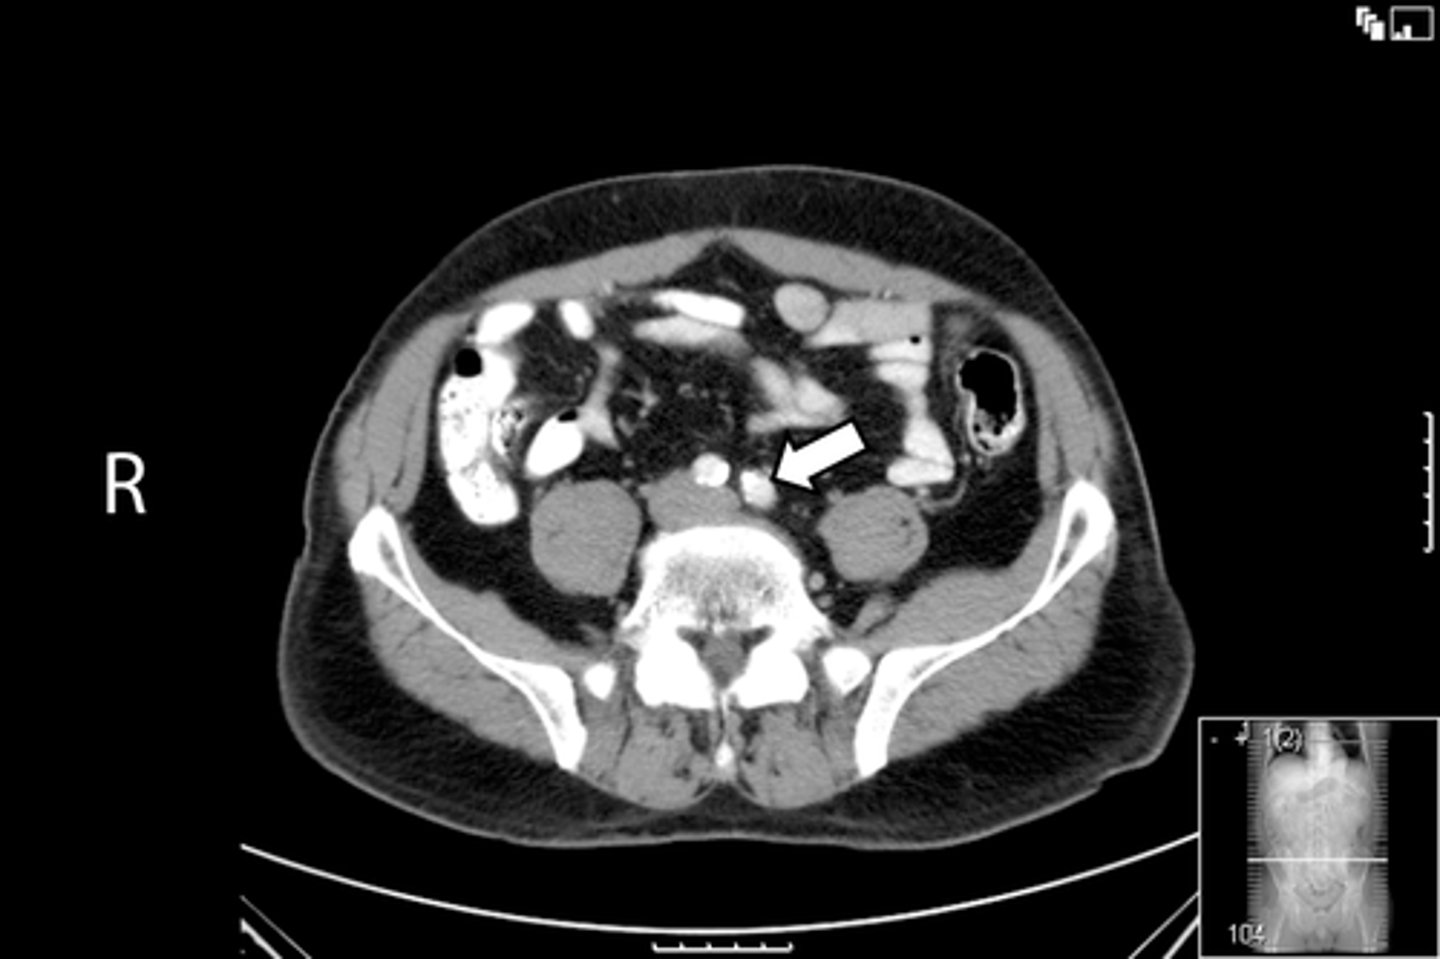

<p>What is indicated in the image?</p>

Axial male pelvis CT

What is the image?

<p>What is the image?</p>

55

New cards

Aorta

What is indicated in the image?

56

Cecum

57

IVC

58

L ilium

59

L psoas muscle

60

R ilium

61

R psoas muscle

62

R rectus abdominis

63

Terminal ilium

64